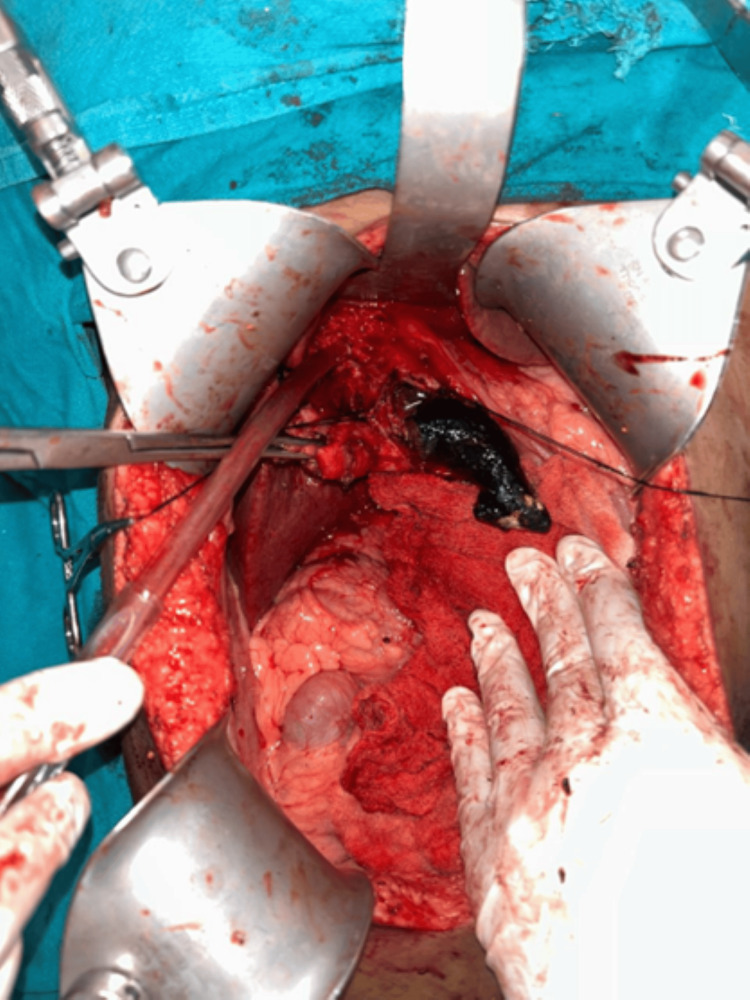

The patient was planned for elective surgery, intraoperatively gall bladder was distended with calculi and had a thickened and fibrotic wall with Frozen Calot’s triangle. Fusiform dilatation of CBD with distal tapering in intra pancreatic portion (Todani classification, type 1c) filled with giant calculi was seen. There was dense adhesion between the CDC and the portal vein. Stone clearance and intraoperative Cholangioscopy were done. The liver had a micronodular surface with pre-cirrhotic changes. We proceeded to separate the cyst from the proper hepatic artery, right hepatic artery (anteromedially), and portal vein (posteriorly). The gall bladder was dissected out from the gall bladder fossa using electrocautery via the Fundus first approach. The cystic duct was ligated and transected and the gall bladder specimen was taken out. Due to dense adhesions present between the CDC and the portal vein, sub-serosal dissection of the CDC was done to prevent injury to the portal vein posteriorly.

Two stay sutures were taken over the choledochal cyst wall laterally. Bile aspirated from the cyst and sent for culture/sensitivity. Choledochotomy was made and bile was aspirated (Figure 4). Giant calculi of approximately 7 cm x 3 cm were retrieved from the CDC (Figure 5). Distal dissection of the intrapancreatic portion was done till ~5 mm proximal to the tapered end. The distal end was transacted and oversewn using PDS 4-0 suture in a double layer. The proximal end was transacted 1 cm distal to the hilum. The cyst wall was sent for histopathology. Proximal jejunum was transacted ~30 cm distal to DJ flexure using a linear cutting blue 60 mm stapler. Cut ends oversewn using prolene 4-0 in a continuous manner. Opening made in transverse mesocolon and distal jejunal limb was delivered in retrocolic fashion. Tension-free end-to-side hepaticojejunostomy was done using prolene 4-0 sutures in an interrupted fashion. A bile leak was noticed from the anastomotic site and two separate sutures were taken at the leak site. Saline wash was given and a 32 Fr abdominal drain was placed in subhepatic space. The side-to-side jejuno-jejunal anastomosis was done using double-layered anastomosis in a continuous fashion (outer layers with prolene 4-0 and inner layers with vicryl 3-0). The postoperative period of the patient was uneventful. The drain was removed on postoperative day 3 and the patient was discharged on postoperative day 7.